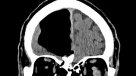

Médicos hallaron un hueco de aire en el cerebro de un hombre

El sujeto de 84 años acudió a un hospital porque se sentía mal. Su historial clínico no indicaba antecedentes extraños, pues no fumaba ni bebía.